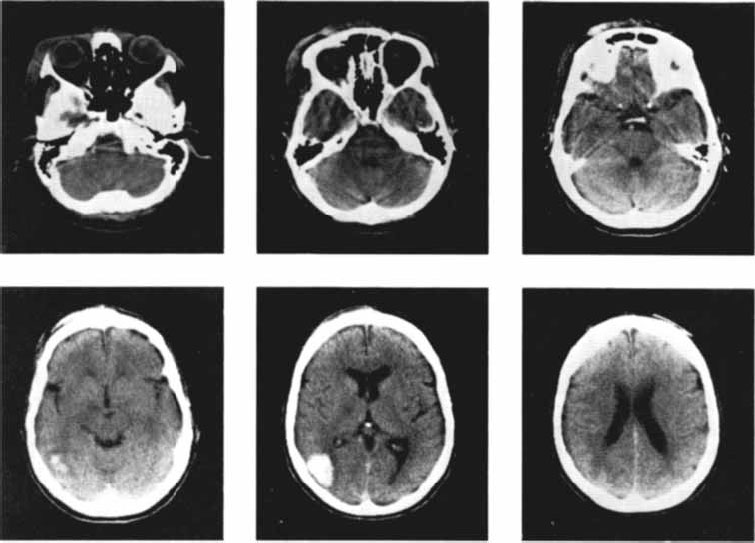

Рис. 2.15. Снимки мозга больных, перенесших инсульт на правой половине мозга, полученные с помощью метода компьютерной томографии (Carlson, 1992).

Для улучшения качества изображения перед исследованием пациенту вводят контрастное вещество. Особенно эффективна компьютерная томо графия для исследования повреждений мозга, например, вследствие инсульта (рис. 2.15), рассеянного склероза, опухолей. Кроме очевидной необходимости этого метода для хирургического исследования перед операциями он представляет значительный интерес для психофизиологов и нейрофизиологов, которые изучают когнитивные процессы и поведение людей, имеющих повреждения мозга.